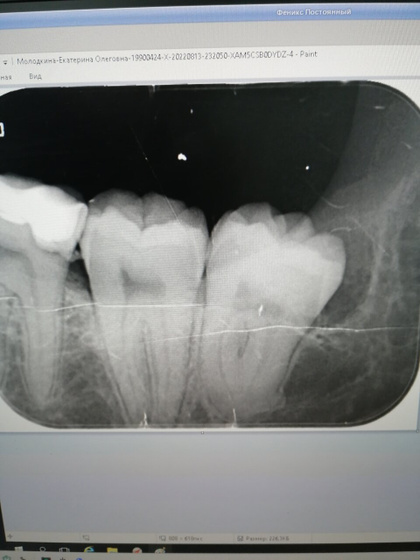

Сфоткала себе снимок, что вчера делали. Ну вдруг в пн в поликлинике опять не работает рентген.

Народу никого. Быстро снимок — обезбол. Вскрыли десну. Рвать не стали, сказали это сложная операция. По записи надо. Ну ок, жду пн.